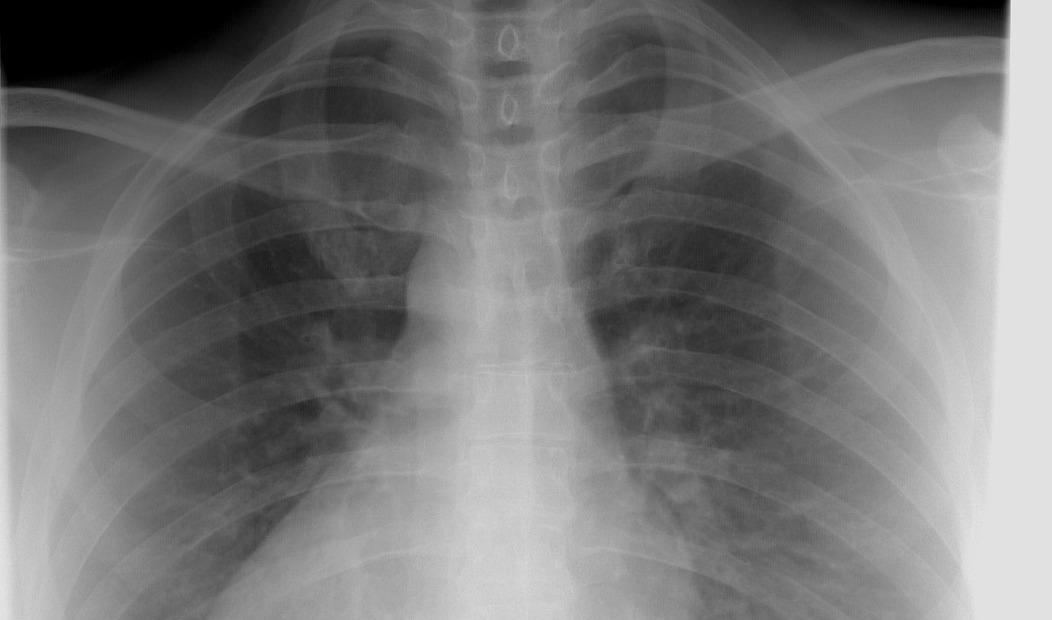

최근에 방문한 병원에서 의사 선생님은 내 영상(방사선 사진)을 보며, 허리도 아플 거라 말씀하셨다. 정작 아파서 찾아간 곳은 등과 어깨였건만, 허리를 연달아 지적하셨다. 나는 웃으며 고개를 저었다.

영상 판독 결과는 놀라웠다. 너덜너덜해졌다던 인대도 아니고, 오십견도 아니었다. 오히려 건강한 어깨였다. 목 디스크가 의심되지만, 염증이 있을 수 있으니 어깨 치료를 우선 받아보기로 했다. 결과는 놀라웠다. 단 한 번의 치료로 어깨와 팔의 통증이 사라졌다.